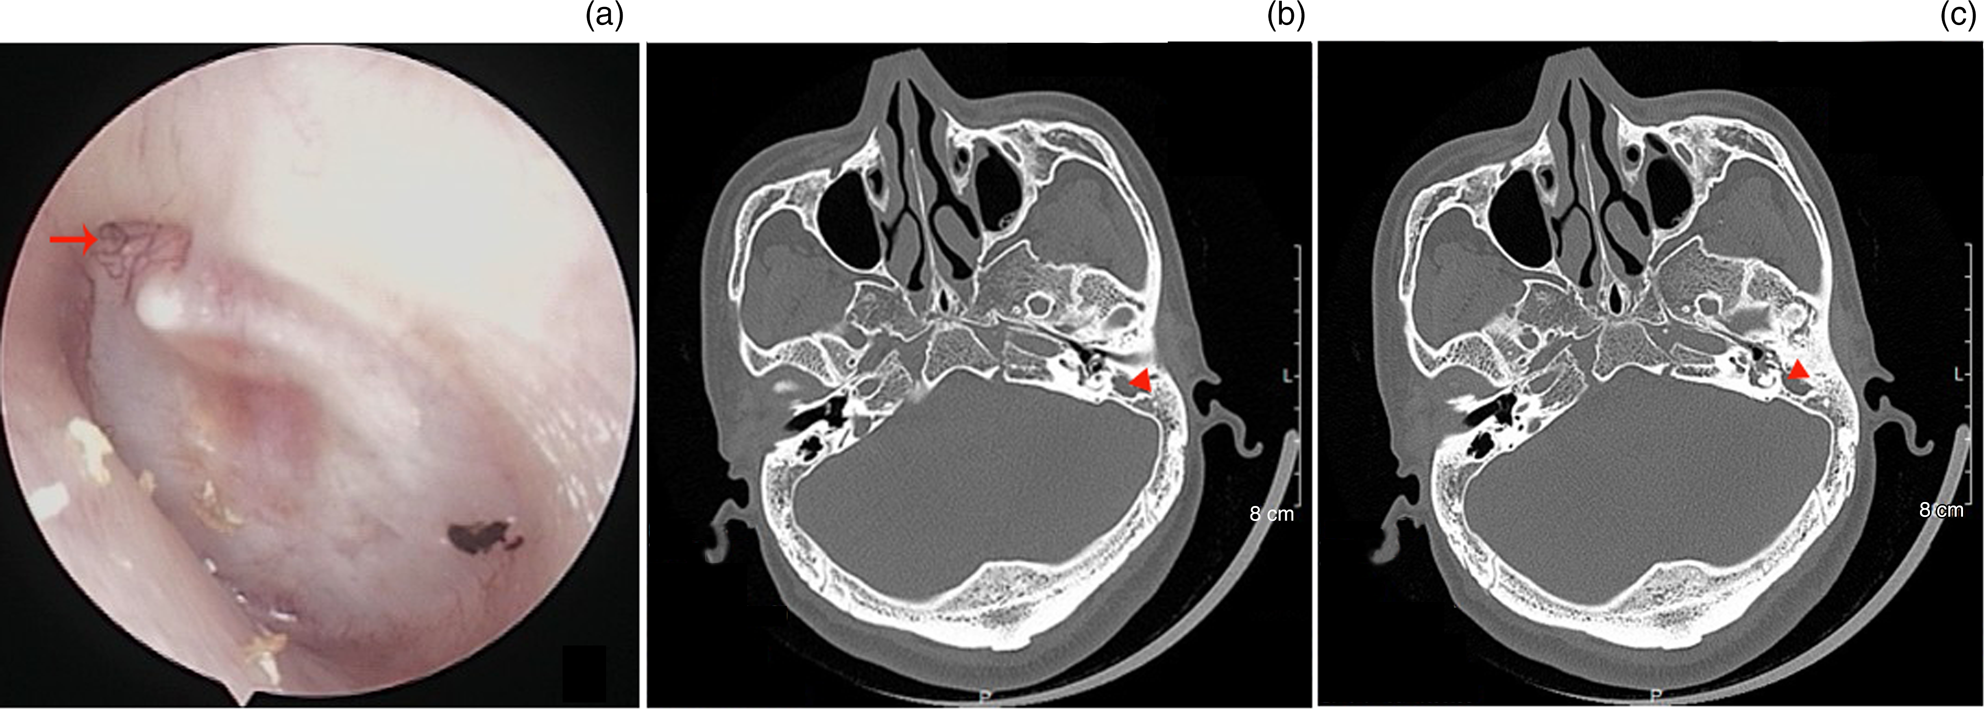

Middleear or mastoid granulation pathology associated with retraction What Is Retraction Pocket In Ear a retracted eardrum is when an air imbalance pulls or sucks in your tympanic membrane (eardrum) toward the. This manuscript intends to review types,. retraction pockets can form on only certain parts of the eardrum instead of the entire membrane. Retraction pocket (rp) of the tympanic membrane is a common entity, especially in children. These tubes drain fluid. What Is Retraction Pocket In Ear.